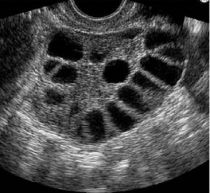

Durante la consulta se pregunta sobre tu ciclo menstrual y tu salud en general, luego se realiza un examen físico completo. Es muy probable que tengas que realizar una prueba de sangre para revisar tus niveles hormonales, los niveles de azúcar en la sangre y el colesterol. También, en la primera consulta se lleva a cabo un ultrasonido para evaluar el estado del útero y los ovarios.

En pacientes que tienen SOP, los ovarios pueden ser un poco más grandes y pueden tener quistes muy pequeños.

¿Tener SOP significa que tengo quistes en los ovarios?

El término “ovarios poliquisticos” significa que tienes muchos quistes pequeñitos o protuberancias dentro de tus ovarios. Algunas mujeres jóvenes con SOP tienen muchos quistes; otras sólo tienen algunos. Aunque tengas muchos, éstos no son dañinos y no necesitan ser extraídos.